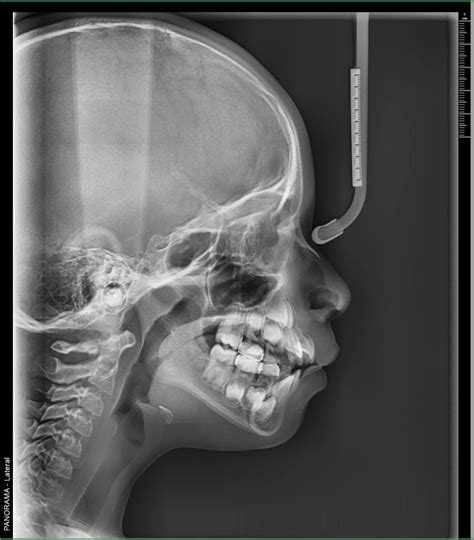

Las radiografías extraorales son técnicas de diagnóstico por imagen en odontología en las que el sensor o película radiográfica se coloca fuera de la boca del paciente. Es fundamental para los análisis cefalométricos que determinan la posición y alineación de los dientes, así como la relación entre los maxilares y el cráneo.

Cefalometría o telerradiografía: es un tipo de radiografía que, en el ámbito odontológico, prácticamente solo se usa en los estudios previos a una ortodoncia.